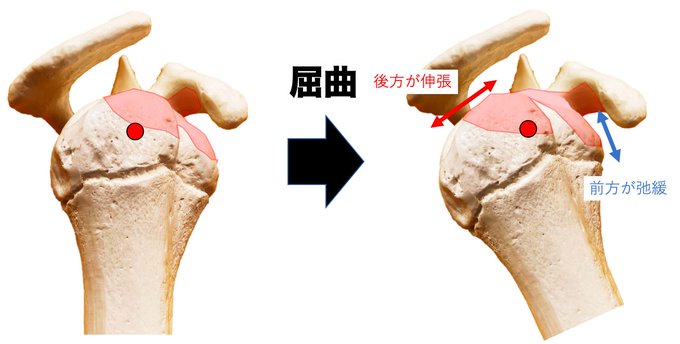

「肩峰下滑液包周囲の軟部組織の位置関係」

何がどうなると、どういった制限になるのか?

憶測レベルではありますが…

自分なりに話をしたいと思っています(^^)